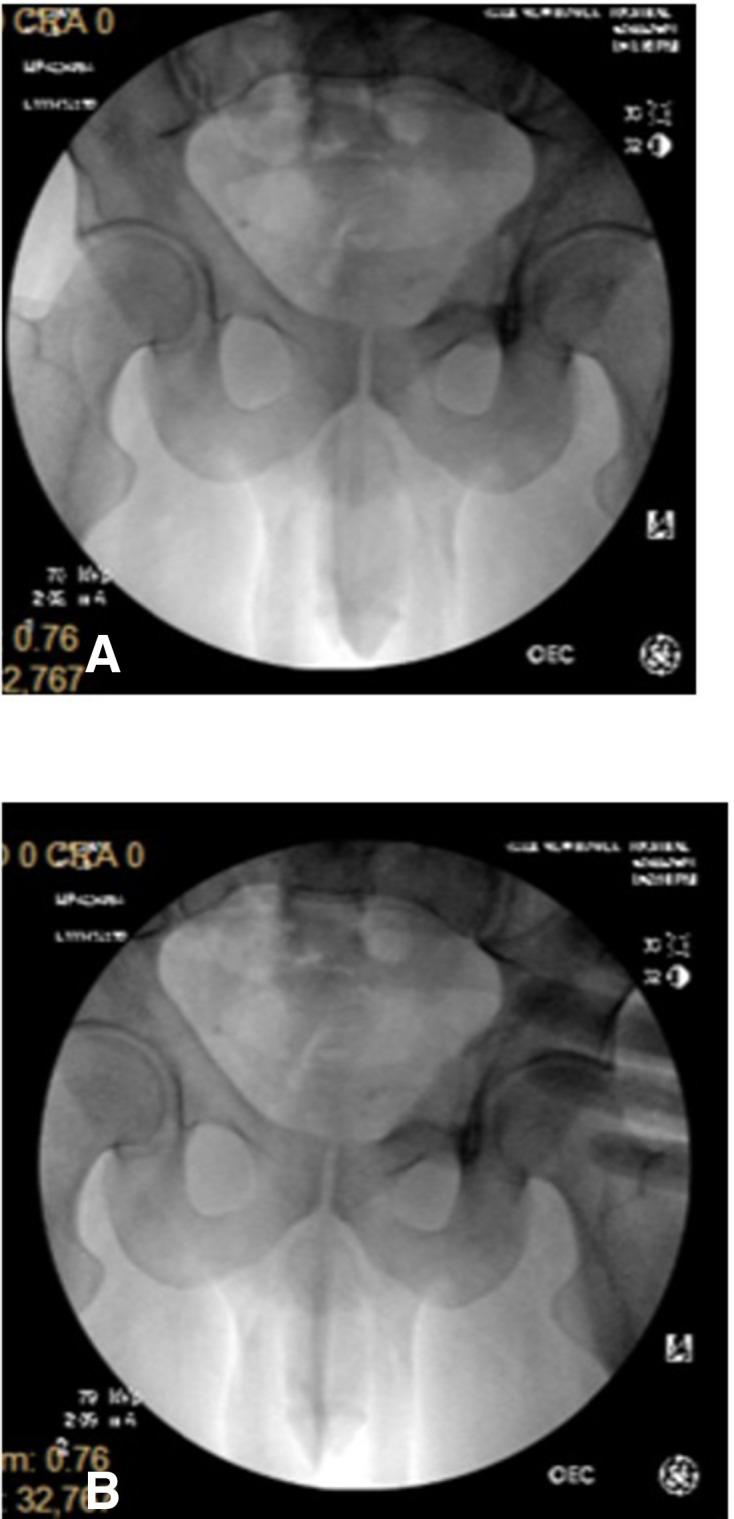

“低致命性”豆袋弹致深部盆腔穿透伤:一例报告及政策启示

“非致命性”弹药旨在使人丧失行动能力,常被执法人员使用。尽管这些弹药并非设计用于造成重伤,但最近的报告表明它们可能导致重伤、永久性残疾和死亡。非致命性弹药所致损伤的长期后果尚不清楚。我们报告一例在延迟就诊的患者中,穿透伤后因残留豆袋弹导致骨髓炎和盆腔脓肿的病例。患者接受了残留豆袋弹的手术取出以及骨髓炎和盆腔脓肿的冲洗和清创,功能恢复良好。我们讨论了非致命性弹药导致严重损伤的公共卫生和政策影响。